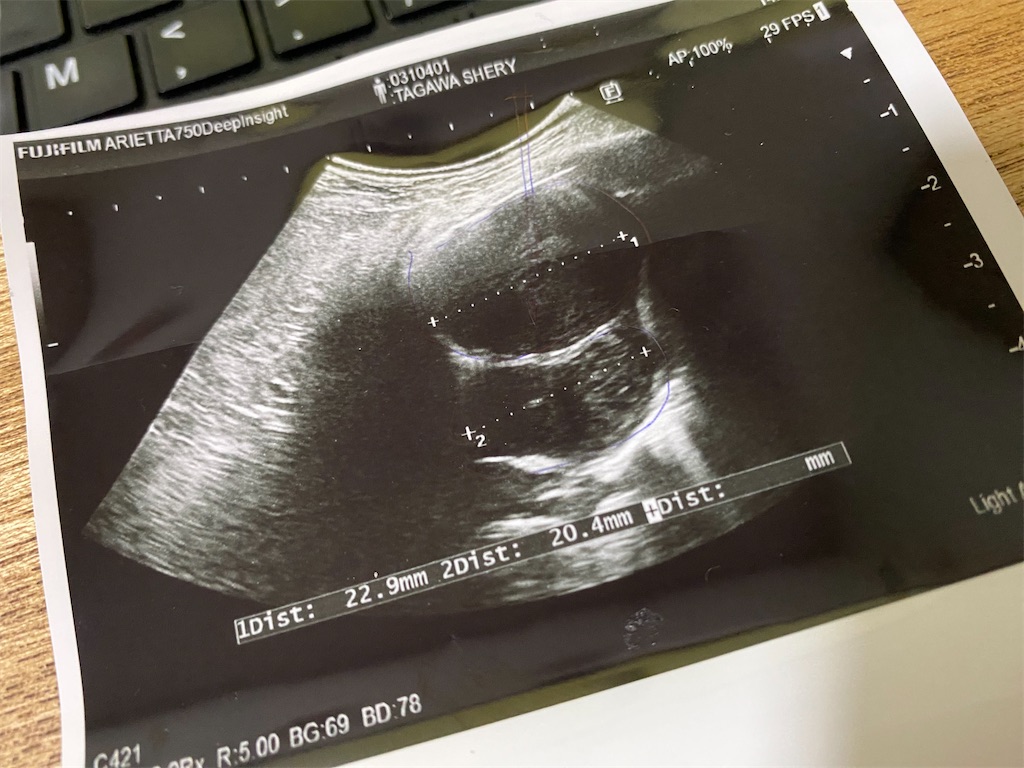

シェリーちゃんの左肺に見つかった病変、原発性腫瘍・膿瘍・巨大気管支粘液栓という診断を受けました。小さな体に2蜂性31㎜の大きな腫瘍。

12月の最終週に手術して1週間程度の入院を提案されました。今回、決して簡単な手術ではなく、ろっ骨を広げて左肺を取り、空いたところに水や空気が溜まらないように処置をするために最低でも1週間が必要ということ。このまま放置していても肺炎を起こせば市のリスクが高まる、手術がうまくいけばまだ2年、3年と生きられる可能性があると。